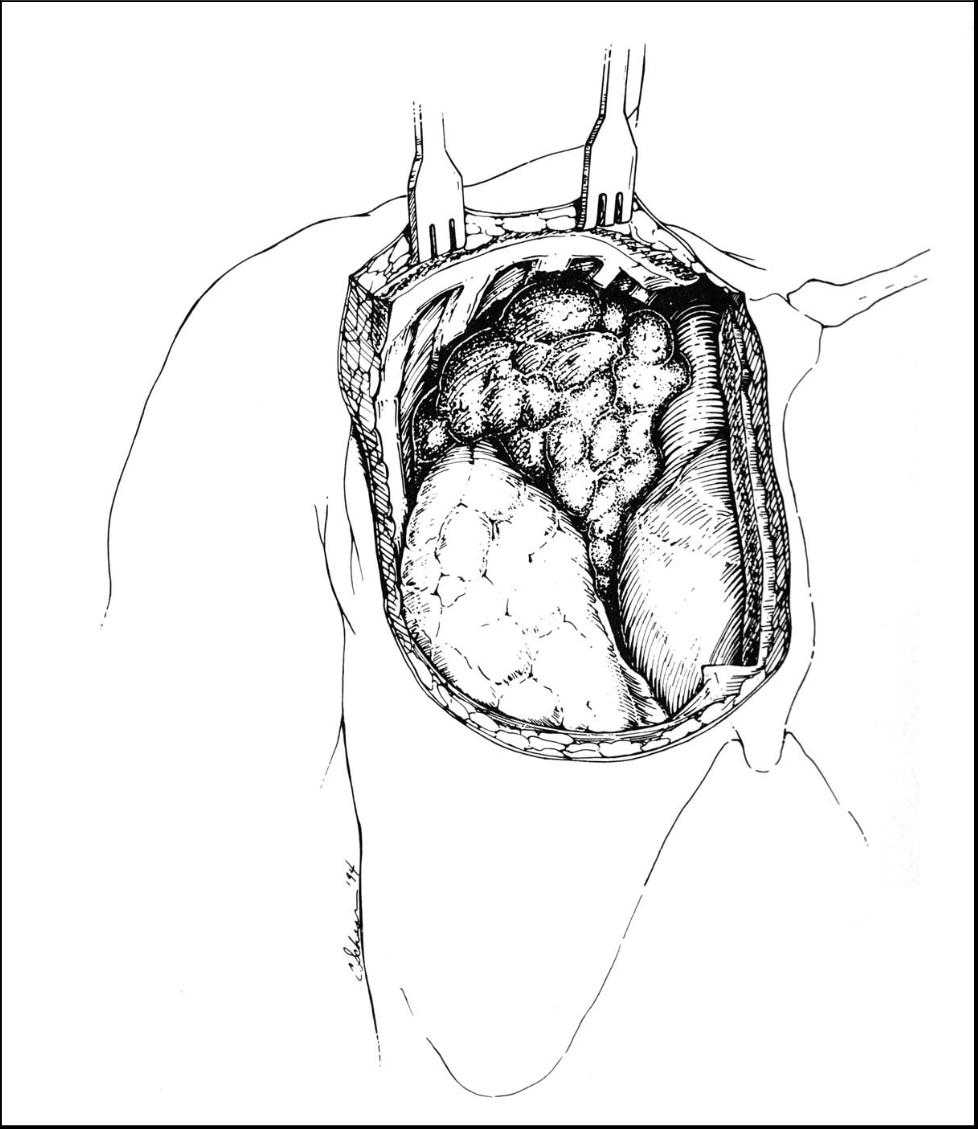

Figure Figure

Figure 4: Incision for a right hemi-clamshell (Bains MS et al. The clamshell incision: an improved approach to bilateral pulmonary and mediastinal tumor. Ann Thorac Surg 1994;58:30-33. Used with permission) Figure 5: Operative exposure for a right hemi-clamshell (Bains MS et al. The clamshell incision: an improved approach to bilateral pulmonary and mediastinal tumor. Ann Thorac Surg 1994;58:30-33. Used with permission)